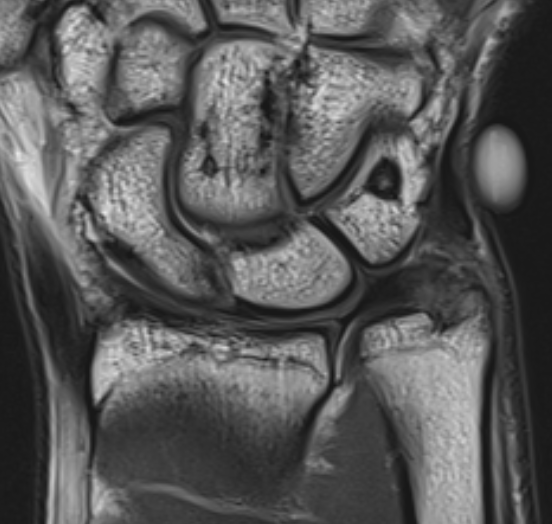

MRI

Kim et al Arch Orthop Trauma Surg 2023

- MRI of 54 patients with distal radius fracture and ulna styloid fracture

- tip ulna styloid fractures: 88% tears TFCC, 41% DRUJ instability after distal radius ORIF

- base ulna styloid fractures: 89% tears TFCC, 57% DRUJ instability after distal radius ORIF

Ulna styloid fracture with TFCC attached to fragment on MRI with partial tearing